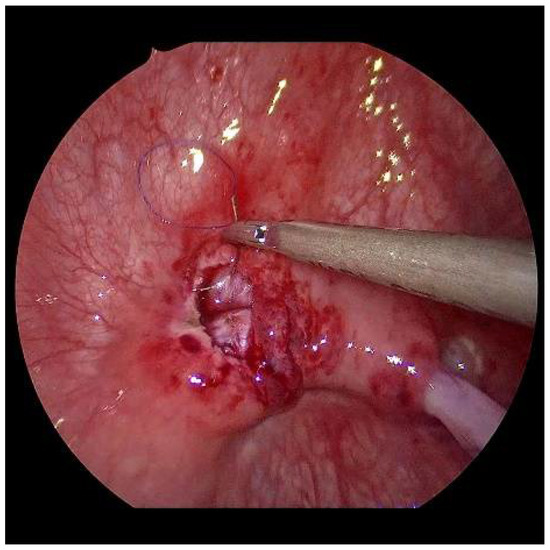

Now, the ureter is intubated with a 3 or 4 Fr. silicone tube, followed by subtle circumferential electrical mucosa incision with a fine dissecting needle (Figure 3). The ureteral release is continued using an electrical hook for at least 4 to 6 cm until it can be positioned without tension to the opposite ostium (Figure 4). Duplicate ureters are intubated twice and mobilized together. If bilateral, the submucosal tunnel is created between the two ostial incisions. If not, an additional mucosal incision is made 1 cm canially of the opposite regular ostium (Figure 5).

Figure 3. For a left-sided VCUR, the ostium is circumferentially incised with a fine needle while gently pulling on the intubated left ureter.